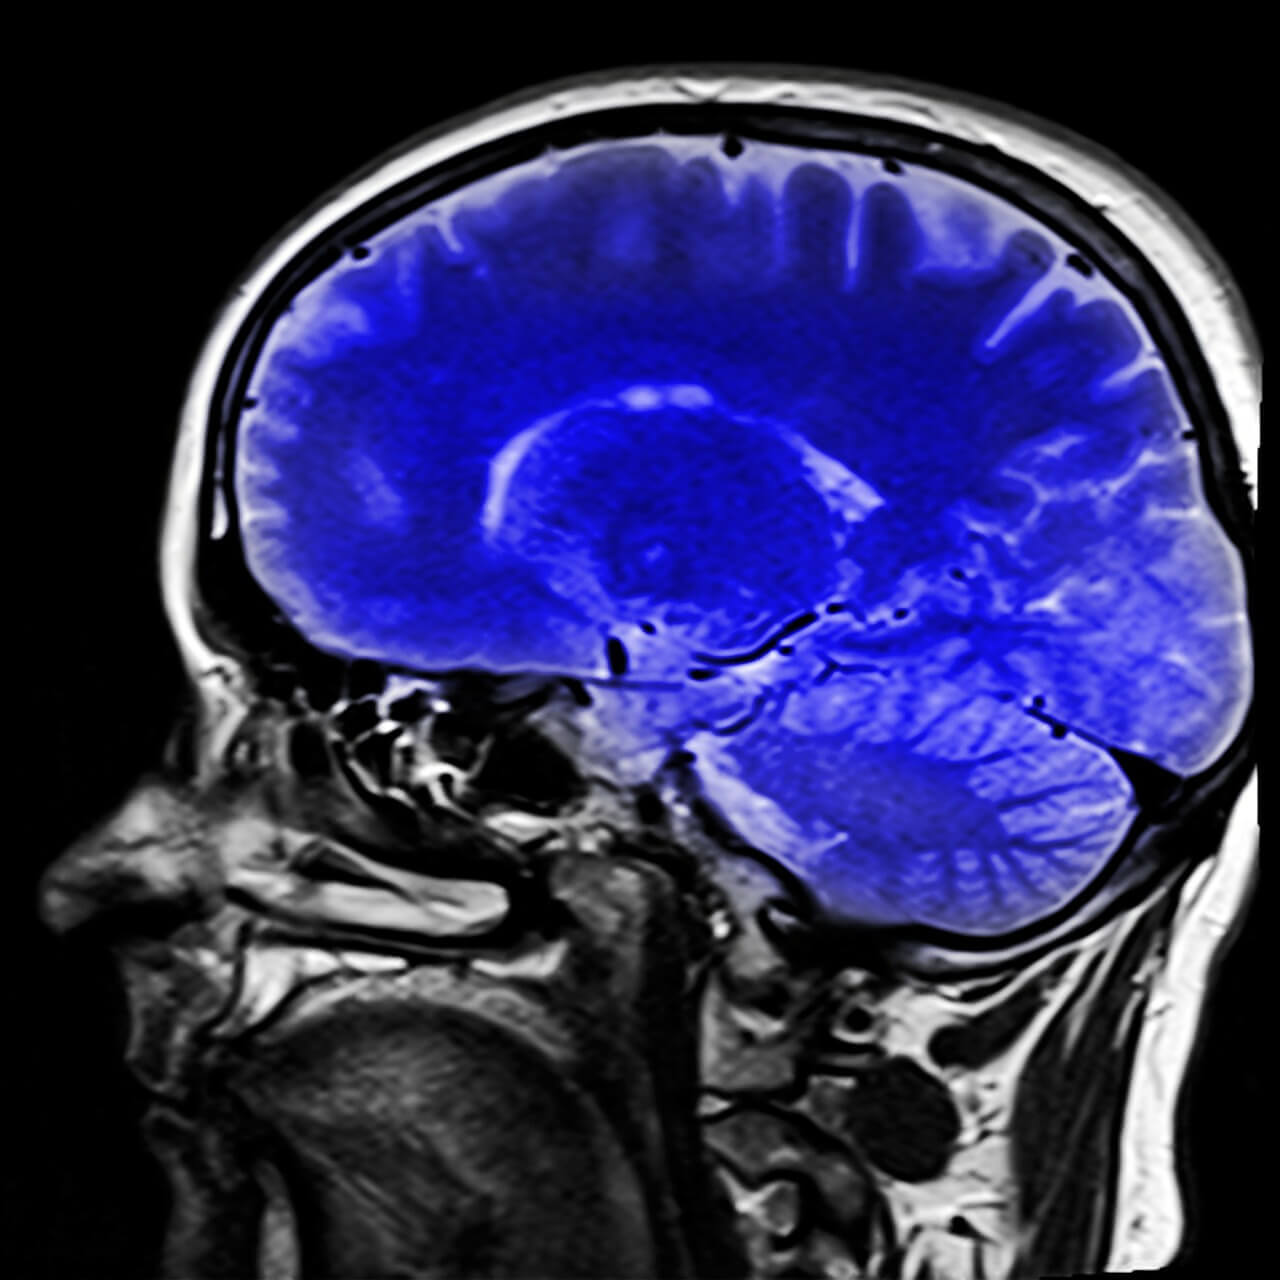

Existen pruebas neurológicas que ayudan al diagnóstico. La resonancia magnética puede mostrar el tipo de lesión cerebral que puede apuntar hacia el síndrome.

Tanto la tomografía por emisión de positrones (PET) como el electroencefalograma (EEG) pueden informar sobre la actividad cerebral. A través del PET se puede observar si el metabolismo cerebral es normal, si ese es el caso, significaría que las funciones cerebrales estarían conservadas y existe conciencia como en el citado síndrome.

A través del EEG se puede monitorizar la actividad de las ondas cerebrales. Colocando unos electrodos en la cabeza, esta herramienta permite determinar las ondas que predominan en el momento. En el caso de una persona que sufriera el síndrome de cautiverio, se encontraría un ritmo alfa posterior reactivo.